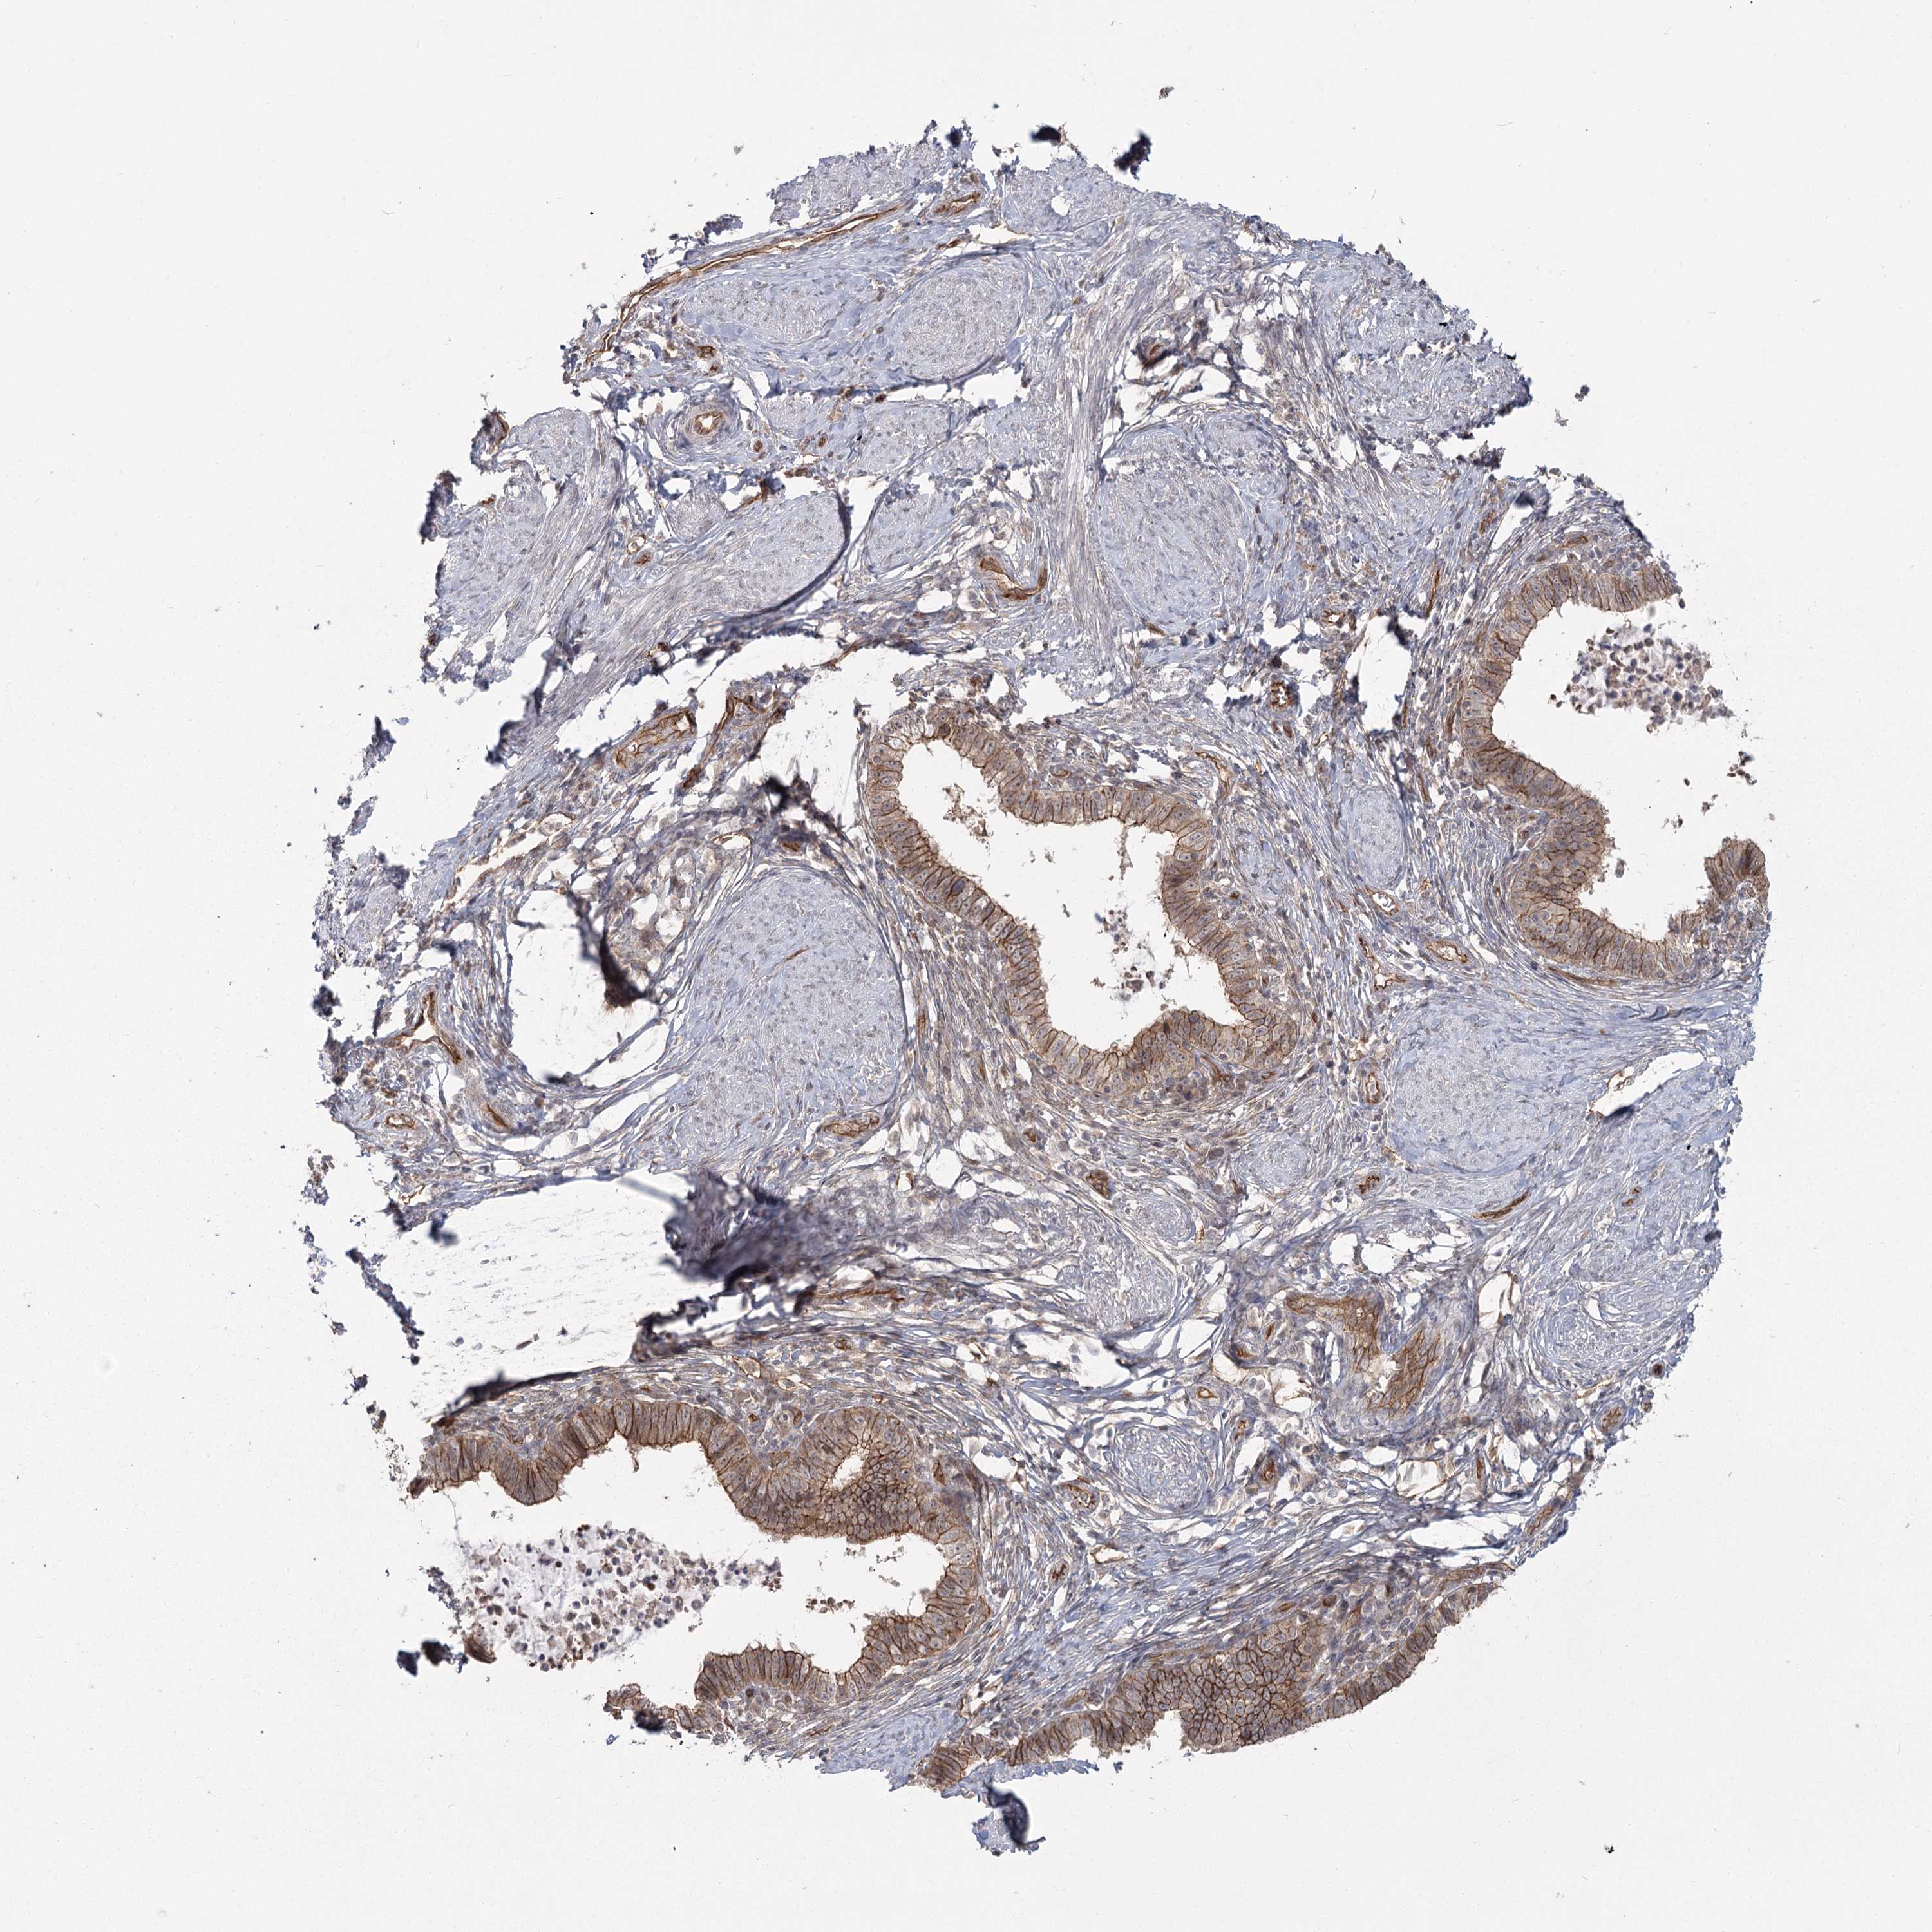

CERVICAL CANCER - Protein expressioni

A mouse-over function shows sample information and annotation data. Click on an image to view it in a full screen mode. Samples can be filtered based on level of antibody staining by selecting one or several of the following categories: high, medium, low and not detected. The assay and annotation is described here.

Note that samples used for immunohistochemistry by the Human Protein Atlas do not correspond to samples in the TCGA dataset.

Antibody stainingi

Antibody staining in the annotated cell types in the current human tissue is reported as not detected, low, medium, or high, based on conventional immunohistochemistry profiling in selected tissues. This score is based on the combination of the staining intensity and fraction of stained cells.

Each image is clickable and will lead to virtual microscopy that enables deeper exploration of all samples and also displays staining intensity scores, fraction scores and subcellular localization as well as patient and tissue information for each sample.

Antibody HPA036194

Staining

High

Medium

Low

Not detected

Intensity

Strong

Moderate

Weak

Negative

Quantity

>75%

75%-25%

<25%

None

Location

Nuclear

Cytoplasmic/membranous

Cytoplasmic/membranous,nuclear

Squamous cell carcinoma, NOS

Adenocarcinoma, NOS